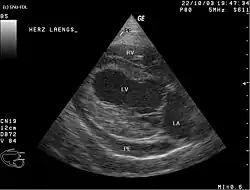

Ein Perikarderguss oder Herzbeutelerguss ist eine pathologische Flüssigkeitsansammlung im Herzbeutel. Eine geringe Menge von Flüssigkeit im Herzbeutel ist nicht krankhaft. Wird diese geringe Menge überschritten, spricht man von einem Perikarderguss. Es gibt akute und chronische Perikardergüsse.

Der Perikarderguss ist ein eher seltener Befund, der meist beim Ultraschall erkannt wird. Punktionswürdige oder punktionsbedürftige Perikardergüsse sind noch einmal seltener. Pleuraergüsse sind vergleichsweise viel häufiger als Flüssigkeitsansammlungen im Herzbeutel.

Bei großen Perikardergüssen sitzen die Patienten aufrecht, sind sehr ängstlich, haben starke Atemnot und gestaute Halsvenen, es besteht meist eine Zyanose; der Puls ist klein und weich. Durch Abklopfen des Brustkorbs kann nur ein sehr großer Erguss festgestellt werden.[3] Die einfachste und schnellste Methode, um einen Erguss zu erkennen, ist der Ultraschall. Auch im CT kann man einen Perikarderguss gut sehen. Die Flüssigkeit des Perikardergusses kann man zytologisch auf maligne Zellen und auf Bakterien untersuchen. Die Punktion des Herzbeutels ist technisch nicht einfach. Je größer der Erguss ist, desto einfacher und zugleich wichtiger ist die Punktion.